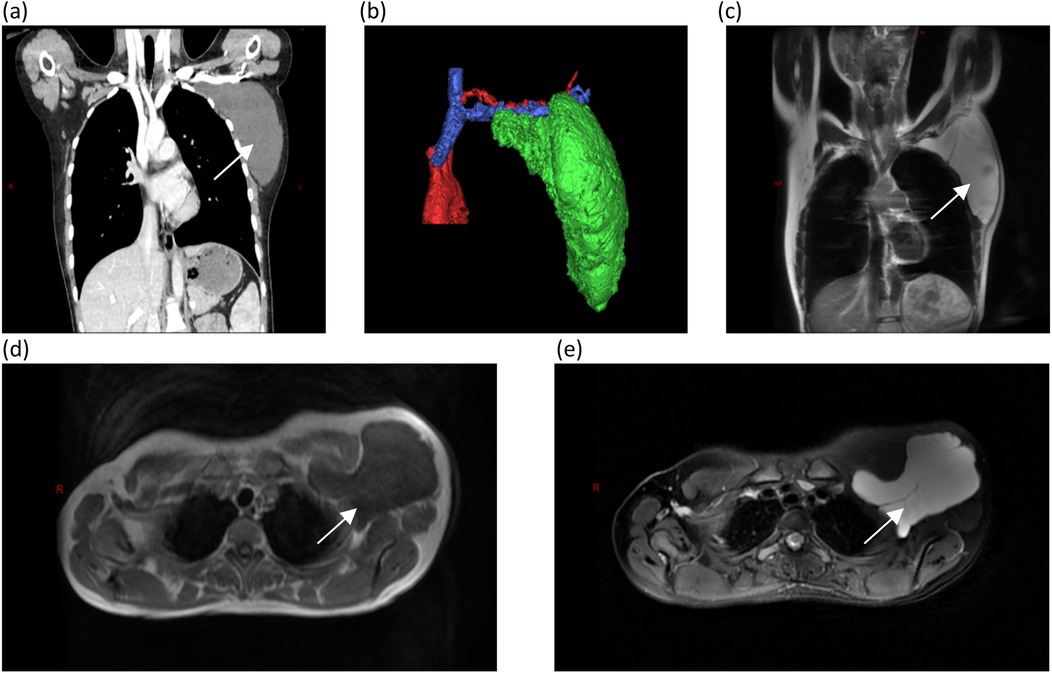

A 17-year-old female patient presented with a chief complaint of a left axillary mass persisting for over 1 month. Past medical history included sclerotherapy for a right facial hemangioma 8 years prior. She denied other illnesses, trauma, smoking, or alcohol use, and her menstrual history was regular. There was no family history of lymphangioma. Her vital signs upon admission were stable. A physical examination revealed normal development and moderate nutrition. The cardiopulmonary and abdominal exams were unremarkable. The local examination identified a 15 cm × 15 cm × 10 cm smooth, non-erythematous, non-ulcerated, soft mass in the left axilla. The mass extended superiorly to the axillary apex, inferiorly to the level of the seventh rib along the posterior axillary line, laterally to the lateral border of the left scapula, and medially beneath the medial third of the left clavicle. It was non-tender, relatively well-defined, and demonstrated limited mobility. Left upper extremity motor and sensory functions were intact. Laboratory investigations were within normal limits. Ultrasonography revealed a well-defined, irregular anechoic area with multiple septations and no significant internal vascularity, suggestive of a lymphatic origin. Computed tomography (CT) and CT angiography (CTA) demonstrated an irregular, non-enhancing, hypodense lesion (CT value 15 HU) in the left axilla, consistent with a cystic lymphangioma. Magnetic resonance imaging (MRI) showed a well-circumscribed, irregular mass exhibiting long T1 and long T2 signal intensity with internal linear short T2 septations, confirming a giant cystic lymphangioma (Figure 1). Aspiration yielded clear, pale yellow fluid, and the cytopathological analysis revealed abundant lymphocytes.

Figure 1. Computed tomography and magnetic resonance imaging, with arrows identifying the mass: (a) CTA revealing a large cystic mass in the left axilla; (b) A three-dimensional reconstruction showing that the mass is adjacent to the subclavian vessels; (c) A coronal view of an MRI examination; and (d,e) long T1 and T2 signals appear hypointense (dark) on T1-weighted images appearing hyperintense (bright) on T2-weighted images.